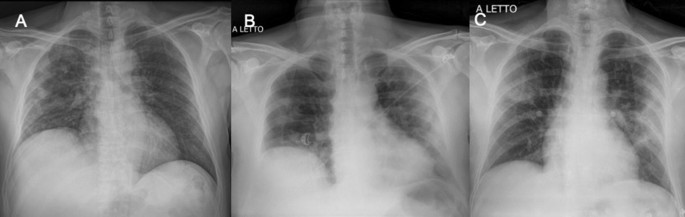

Chest X Ray And Ct Findings Of Young Covid 19 Patients Undergoing Non Invasive Treatment Eurorad